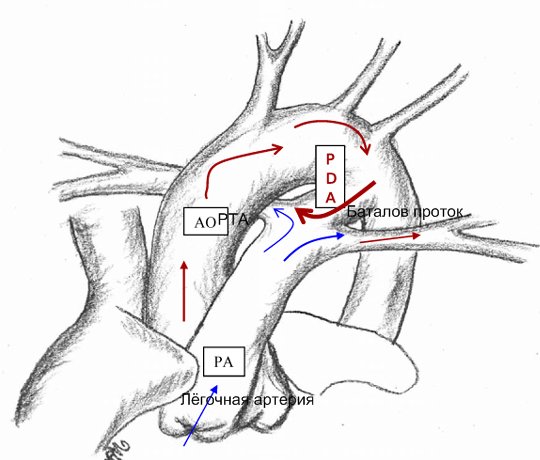

Открытый Баталов проток — это заболевание сердца, которое появляется у детей вскоре после рождения. С помощью Баталова протока соединяются два главных сосуда, отходящих от сердца, - лёгочная артерия и аорта. В утробе эти сосуды должны быть соединены, так кровь не должна поступать в неработающие лёгкие плода. Кислород она получает от матери,и поэтому кровь поступает из лёгочной артерии в аорту, минуя лёгкие. В норме в течение нескольких минут — нескольких дней после рождения Баталов (артериальный) проток закрывается. У некоторых детей он остаётся открытым, тогда артериальная кровь в аорте, богатая кислородом, будет смешиваться с венозной кровью, бедной кислородом. Это приведёт к нарушению снабжения органов и тканей кислородом, а вследствие этого к нарушению их функционирования.